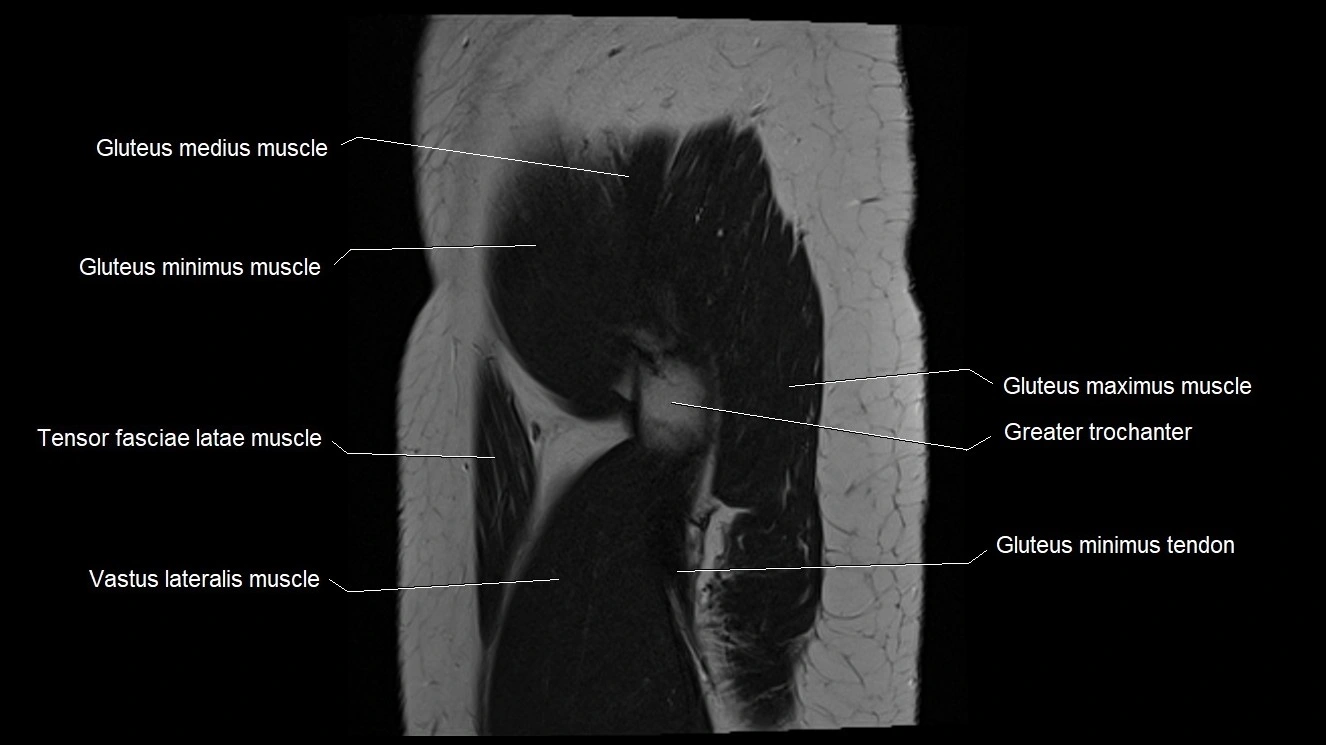

- Gluteus maximus muscle

- Gluteus medius muscle

- Gluteus medius tendon

- Gluteus minimus muscle

- Gluteus minimus tendon

- Greater trochanter

- Iliotibial tract

- Tensor fasciae latae muscle

- Vastus lateralis muscle